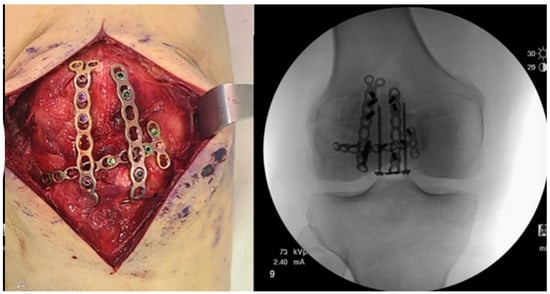

2.5. Locking Plates

- Wild, M.; Fischer, K.; Hilsenbeck, F.; Hakimi, M.; Betsch, M. Treating patella fractures with a fixed-angle patella plate-A prospective observational study. Injury 2016, 47, 1737–1743. [Google Scholar] [CrossRef] [PubMed]

- Buschbeck, S.; Götz, K.; Klug, A.; Barzen, S.; Gramlich, Y.; Hoffmann, R. Comminuted AO-C3 fractures of the patella: Good outcome using anatomically contoured locking plate fixation. Int. Orthop. 2022, 46, 1395–1403. [Google Scholar] [CrossRef]

- Yoo, S.J.; Ok, S.; Lee, J.; Choi, S. Can multiple miniplates improve the treatment of comminuted patellar fracture? BMC Musculoskelet. Disord. 2023, 24, 936. [Google Scholar] [CrossRef] [PubMed]

- Amin, A.; Kellam, P.J.; Warner, S.J. Treatment of a Multifragmentary Patella Fracture Using a Novel Anatomic Locking Plate. J. Orthop. Trauma 2022. [Google Scholar]